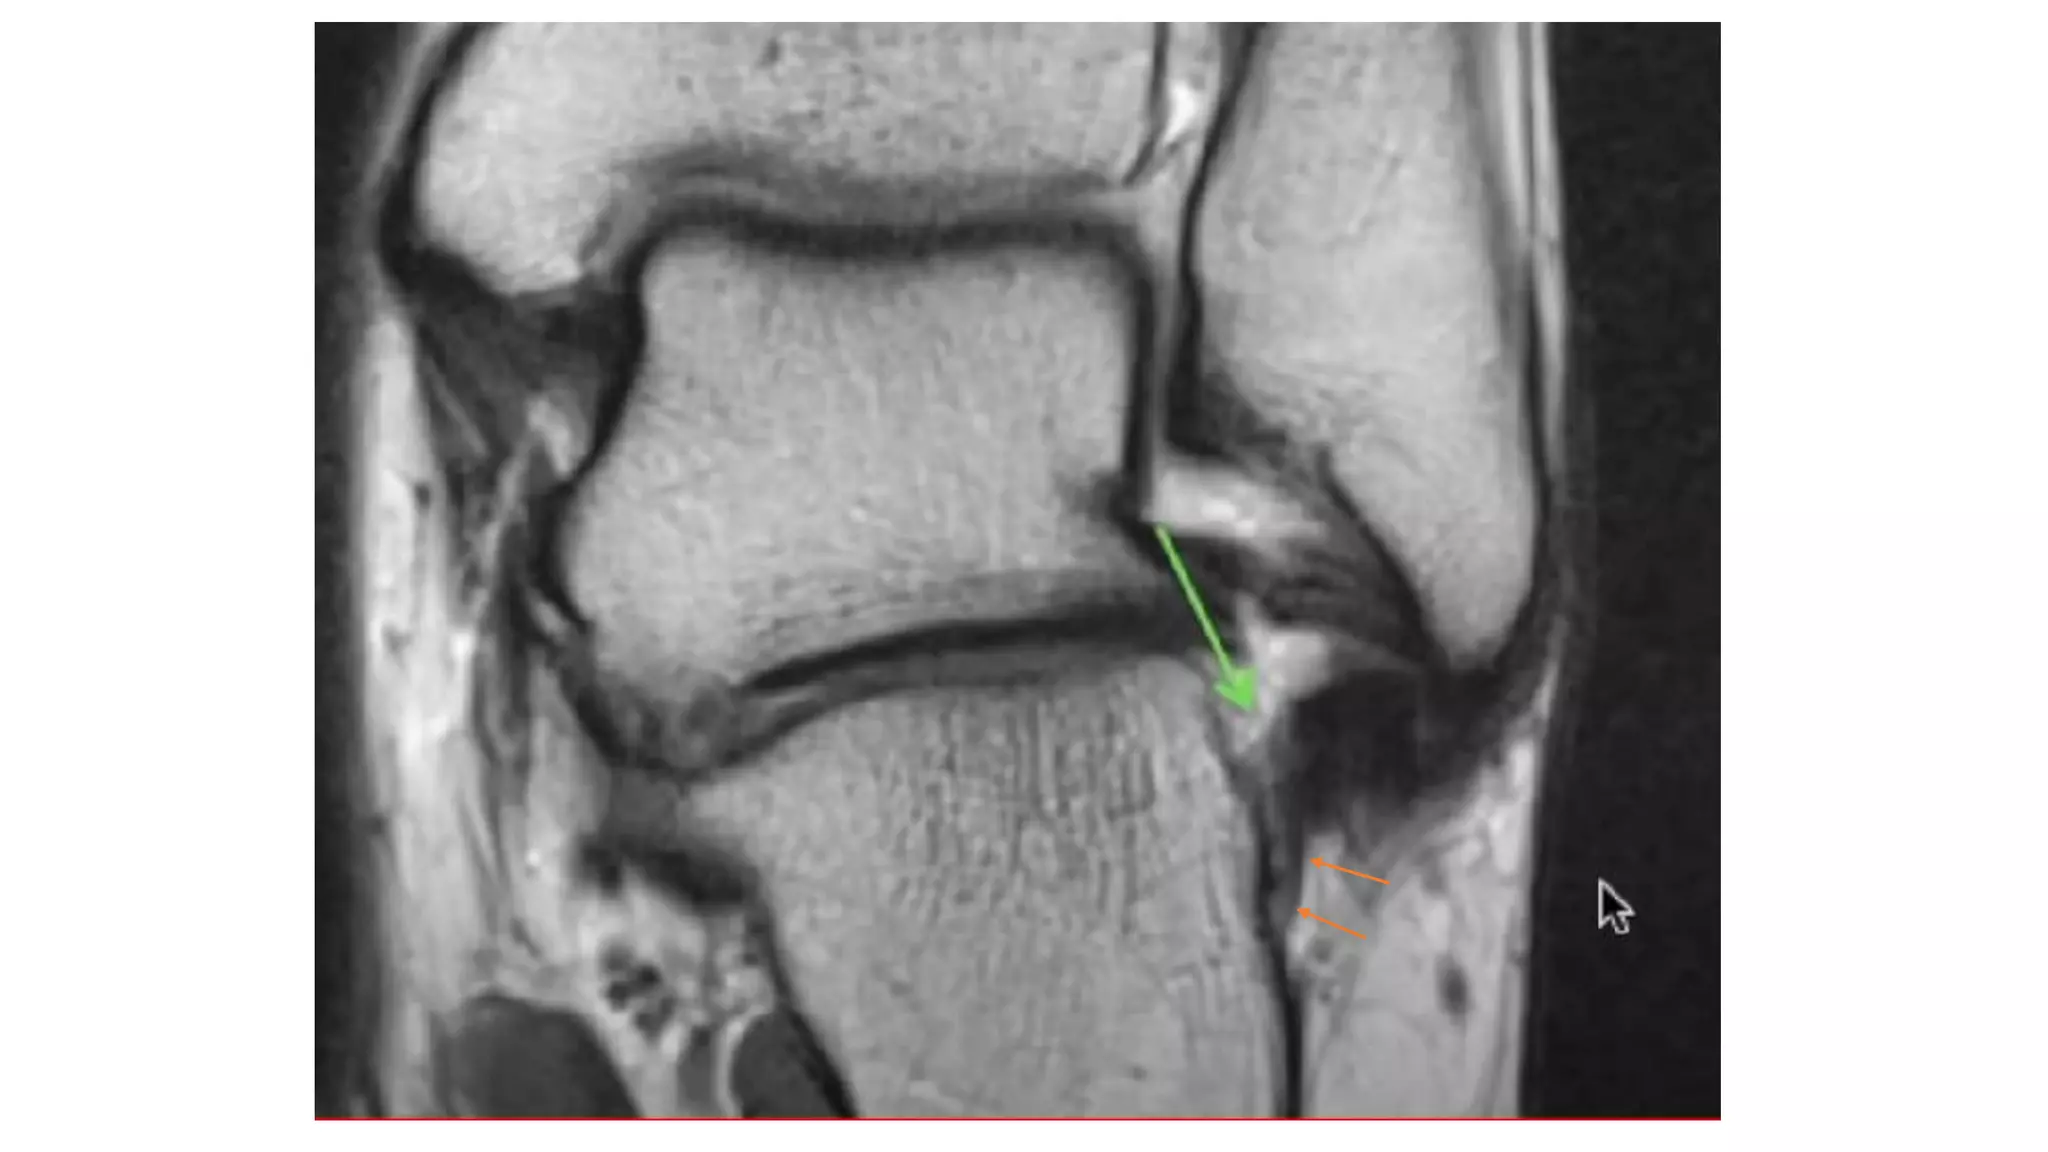

This MRI ankle report describes the anatomy of the ankle, including ligaments such as the anterior and posterior tibiofibular ligaments, syndesmosis ligaments, deltoid ligament, and calcaneofibular ligament. It outlines the tendons in the anterior, lateral, medial, and posterior compartments, including the tibialis posterior, peroneus, flexor hallucis longus, and Achilles tendons. The sinus tarsi is also noted.